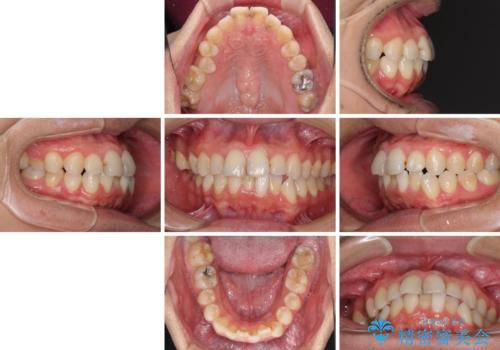

顎が左右にずれた咬み合わせ ハーフリンガルの抜歯矯正

- 口元の突出感を気にして来院された患者様です。

目立たない装置を希望され、上顎が裏側装置で下顎が表側装置のハーフリンガルを希望されました。

上下の顎骨が左右に大きくずれており、奥歯が交叉咬合となっていたため、ハーフリンガルよりも表側装置をおすすめしましたが、目立たない装置を強く希望されたため、治療期間が長期化することを前提に、ハーフリンガルにて抜歯矯正を行うこととしました。